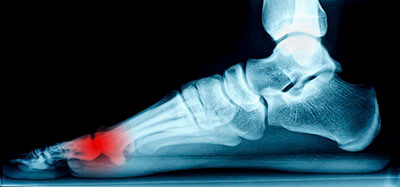

Mortons' neuroma specialist in the Palm Beach County, FL: Boynton Beach (Kings Point, Westgate, Delray Beach, Boca Raton, Manalapan, Greenacres, Palm Springs) and Palm Beach Gardens (Juno Beach, Lake Park, Riviera Beach, Jupiter, Tequesta, Mangonia Park, Cloud Lake, Limestone Creek, Cabana Colony), and West Palm Beach (Hypoluxo, Wellington, Haverhill, Loxahatchee Groves, Lake Worth, Lantana, Golden Lakes) areasThe pain caused by Morton’s neuroma is typically experienced at the ball of the foot. Many have described the sensation as feeling like they have a pebble stuck in their shoe. Because of this, those with the condition may find walking to be more difficult and uncomfortable. They may also experience a numbing or burning sensation in the foot. One of the most common factors that influence the development of Morton’s neuroma is improper footwear. Those who generally wear tightly fitted shoes or shoes with higher heels are more at risk at getting Morton’s neuroma. Having a foot abnormality may also increase the risk of getting this condition, as it may cause instability, thus adding more pressure onto the nerves of the foot. Certain foot conditions such as bunions, hammertoes, and flat flat feet have also been known to lead to Morton’s neuroma if not treated promptly.

Neuromas can be caused by anything that causes compression or irritation of the nerve. A common cause is wearing shoes with tapered toe boxes or high heels that force the toes into the toe boxes. Physical activities that involve repeated pressure to the foot, such as running or basketball, can also create neuromas. Those with foot deformities, such as bunions, hammertoes, or flat feet, are more likely to develop the condition.